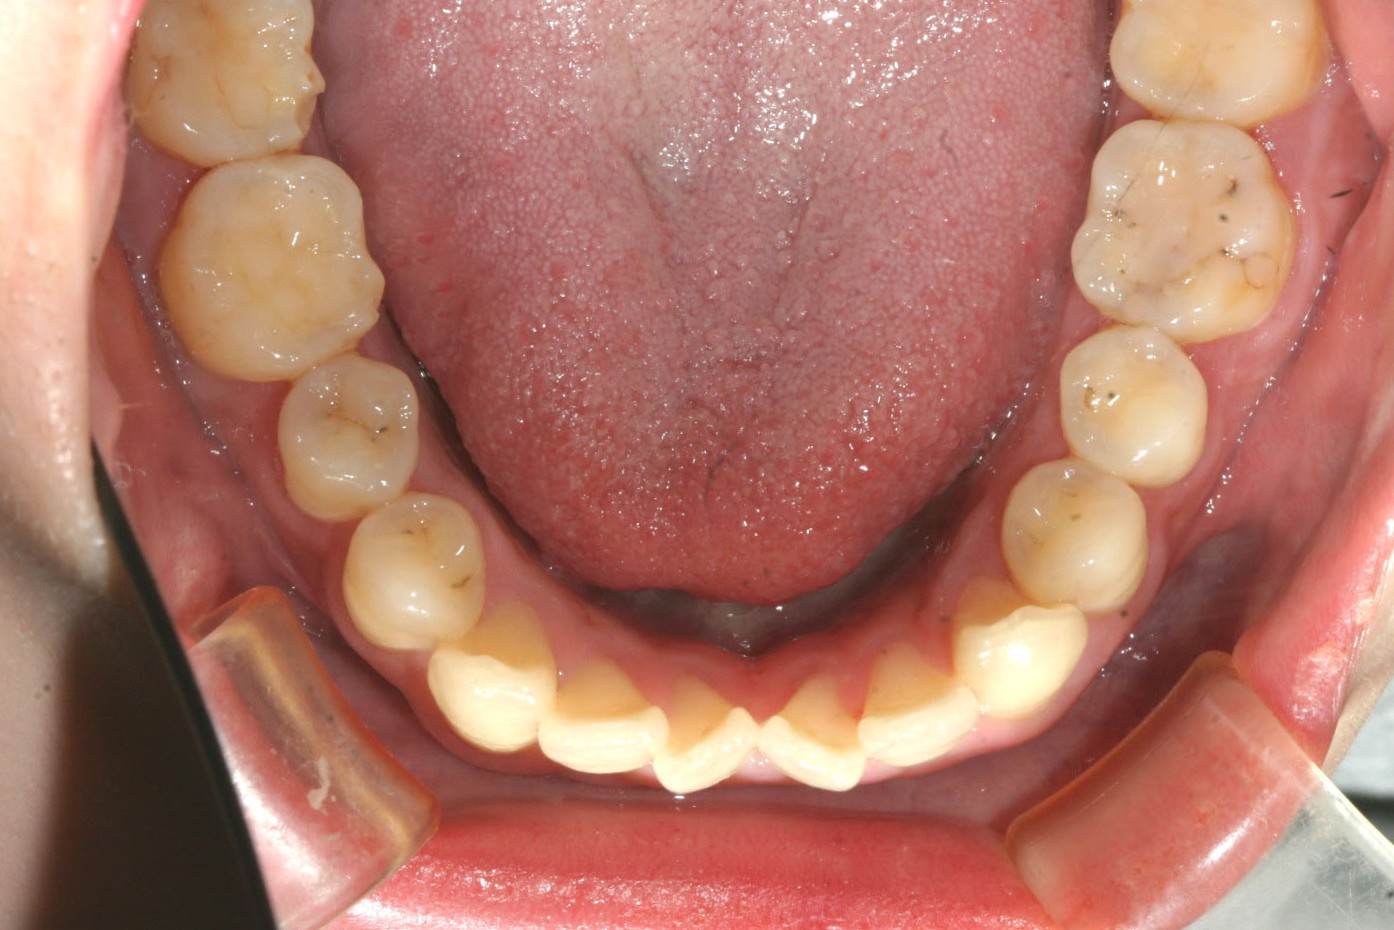

下顎もアーチが狭い為前歯にしわ寄せがきて翼状捻転していますね~

下顎もアーチを広げ綺麗に並びました。